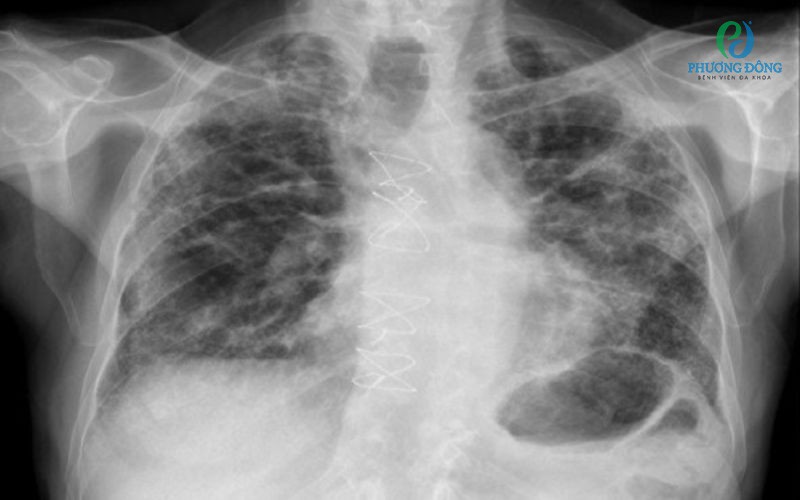

Người từng mắc Covid-19, đặc biệt thuộc nhóm có nguy cơ cao, nên khám sàng lọc di chứng phổi. Bác sĩ sẽ khai thác tiền sử bệnh, kiểm tra khả năng vận động và chỉ định các xét nghiệm cần thiết như:

• Chụp cắt lớp vi tính (CT scan) lồng ngực.